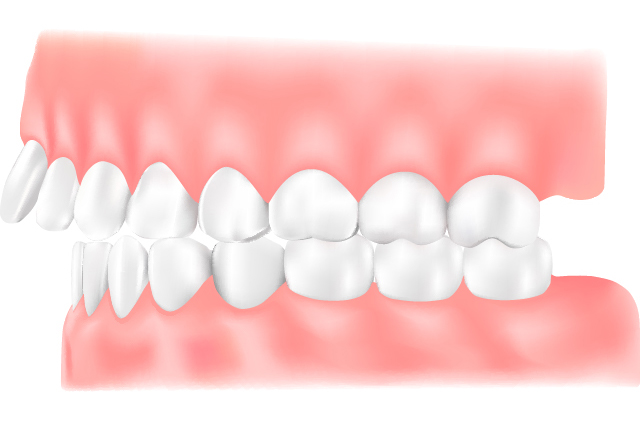

上顎前突(出っ歯)

上の歯が前方に傾斜して生えている状態、または下の歯全体が後方に位置することで出っ歯に見える状態です。唇を切ってしまったり、顔を強打した際に歯が折れやすくなることがあります。